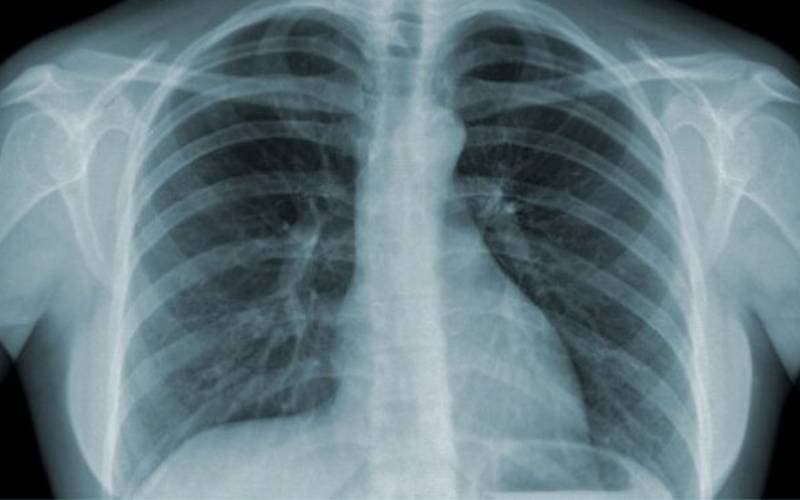

3.1. Hình ảnh viêm phế quản trên phim X-quang và nội soi

– X-quang lồng ngực: Giúp phát hiện tình trạng viêm nhiễm hoặc tăng tiết dịch nhầy trong phế quản.

Hình ảnh chụp Xquang viêm phế quản